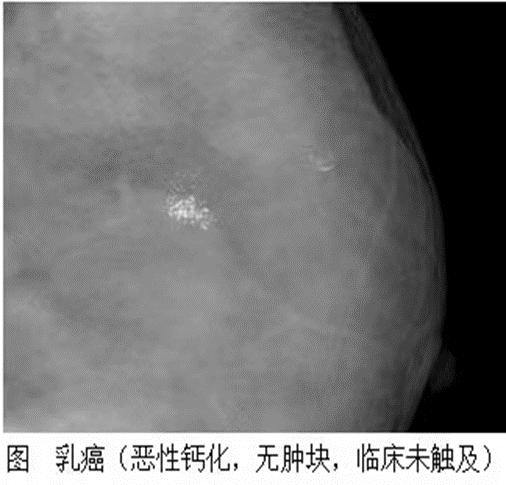

钼靶对微钙化(砂砾样、点簇状)非常敏感,因此对乳腺肿块良恶性的鉴别更有优越性,尤其对还没有形成结节的早期乳腺癌的诊断非常有价值。

对钙化不敏感,尤其容易忽略砂砾样、点簇状的微钙化,而这些钙化往往提示肿块可能是恶性的。另外超声对非肿块性乳腺癌检出率低,容易漏诊。